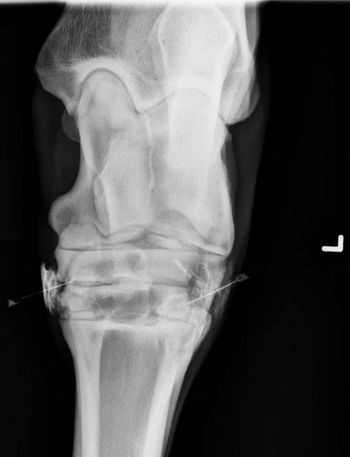

Are you an X-ray expert? Test your skills with this case of an unsteady standard poodle pup.

Many clients want the easiest or cheapest solutionbut its not that simple, says Dr. David Dycus. Each decision has to be made on a case-by-case basis.